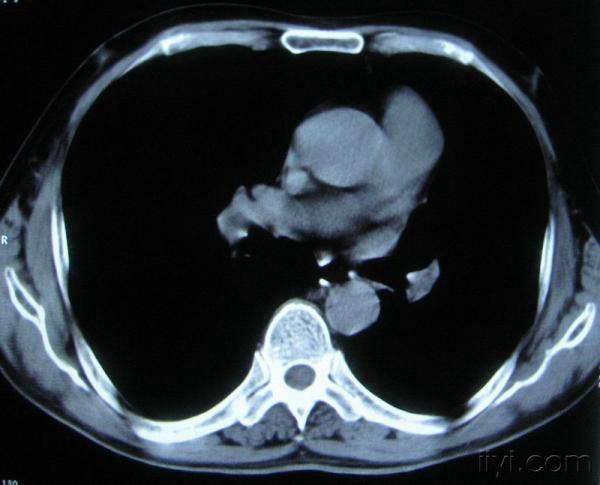

男。60岁,胸片示支气管炎治疗后复查CT。

你指那个肯定是淋巴结,中央系坏死,这很常见,特别在双侧腹股沟会经常看到。这个双侧腋窝及纵隔见多发小淋巴结征。

根据位置考虑应该是淋巴结,密度不均,是因为肿大的淋巴结中心液化坏死